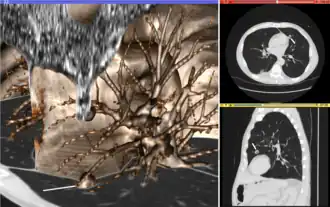

Visualization plays several key roles in medical image computing. Methods from scientific visualization are used to understand and communicate about medical images, which are inherently spatial-temporal. Data visualization and data analysis are used on unstructured data forms, for example when evaluating statistical measures derived during algorithmic processing. Direct interaction with data, a key feature of the visualization process, is used to perform visual queries about data, annotate images, guide segmentation and registration processes, and control the visual representation of data (by controlling lighting rendering properties and viewing parameters). Visualization is used both for initial exploration and for conveying intermediate and final results of analyses.

The figure "Visualization of Medical Imaging" illustrates several types of visualization: 1. the display of cross-sections as gray scale images; 2. reformatted views of gray scale images (the sagittal view in this example has a different orientation than the original direction of the image acquisition; and 3. A 3D volume rendering of the same data. The nodular lesion is clearly visible in the different presentations and has been annotated with a white line.